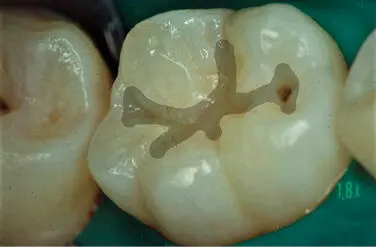

Figura 310En los puntos y fisuras no involucrados se coloca un sellador de - фото 36

Figura 3.10.En los puntos y fisuras no involucrados se coloca un sellador de puntos y fisuras.